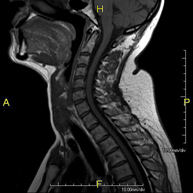

- RM Columna cervical

Prueba diagnóstica no invasiva que consiste en la obtención de imágenes de alta definición anatómica de la columna cervical mediante el empleo de un campo electromagnético y ondas de radio (con un emisor y un receptor). No utiliza radiación ionizante. Indicaciones: traumatismo, degeneración de la columna, hernias.